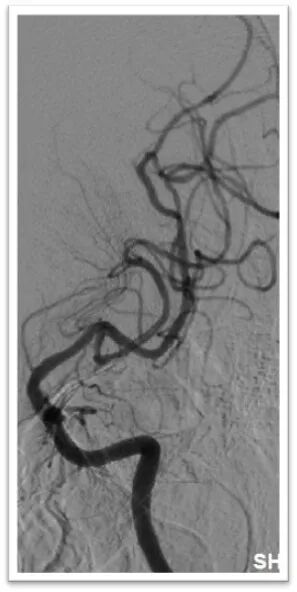

微导丝引导微导管顺利置于左侧大脑中动脉上干,半释放6-30mm支架,停留5分钟后完全取出血栓,造影显示左侧大脑中动脉血流完全恢复,mTICI:3级。

术后即刻造影结果